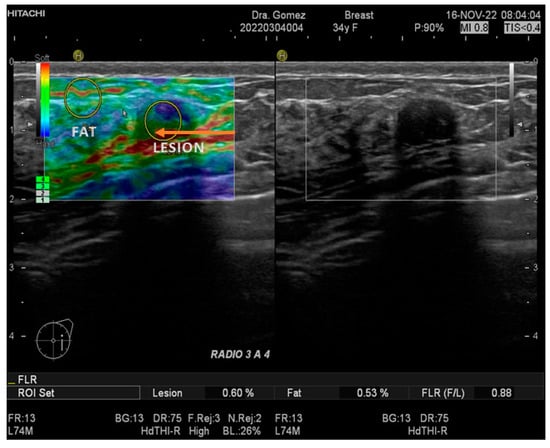

2.2. Ultrasound and Strain Elastography